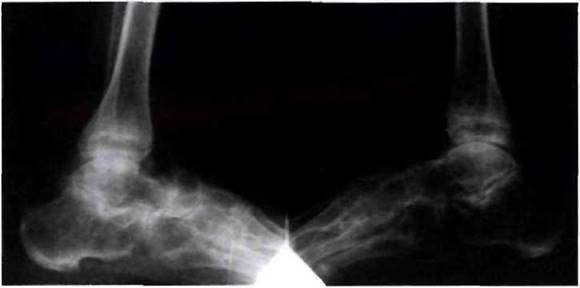

Рис. 23-5. Рентгенограмма стоп больного ювенильным спондилоартритом: деструкция в суставах предплюсны, крупные остеофиты, эрозии, резкое сужение щелей.

Рис. 23-6. Рентгенограмма стоп больного ювенильным анкилозирующим спонилоартритом: «анкилозирующий тарзит».